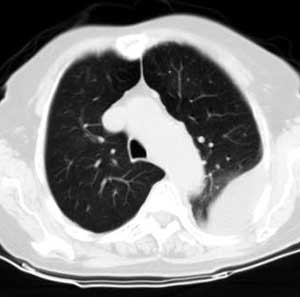

请上传纵隔窗。目前还是支技包裹性积液(明显梭形),即使是间皮瘤并积液也少梭形的。

从图片看,包裹性积液好象更合理,梭形,ct值3-5hu(在哪看到的?);胸膜间皮瘤如此规则,不多见。

左侧背部胸膜肥厚,伴包裹性积液,不考虑间皮瘤.

同意以上各位的高见,首先考虑包裹性积液,1.胸膜间皮瘤积液量一般较大,以游离性积液更为常见,2.可以看到增厚的胸膜结节